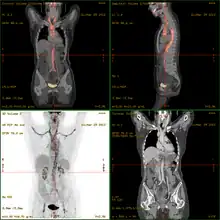

- 18F-fluorodeoxyglucose positron emission tomography/computed tomography (FDG-PET/CT)has become a widely used imaging tool in patients with suspected Large Vessel Vasculitis, due to the enhanced glucose metabolism of inflamed vessel walls.[15] The combined evaluation of the intensity and the extension of FDG vessel uptake at diagnosis can predict the clinical course of the disease, separating patients with favourable or complicated progress.[16]